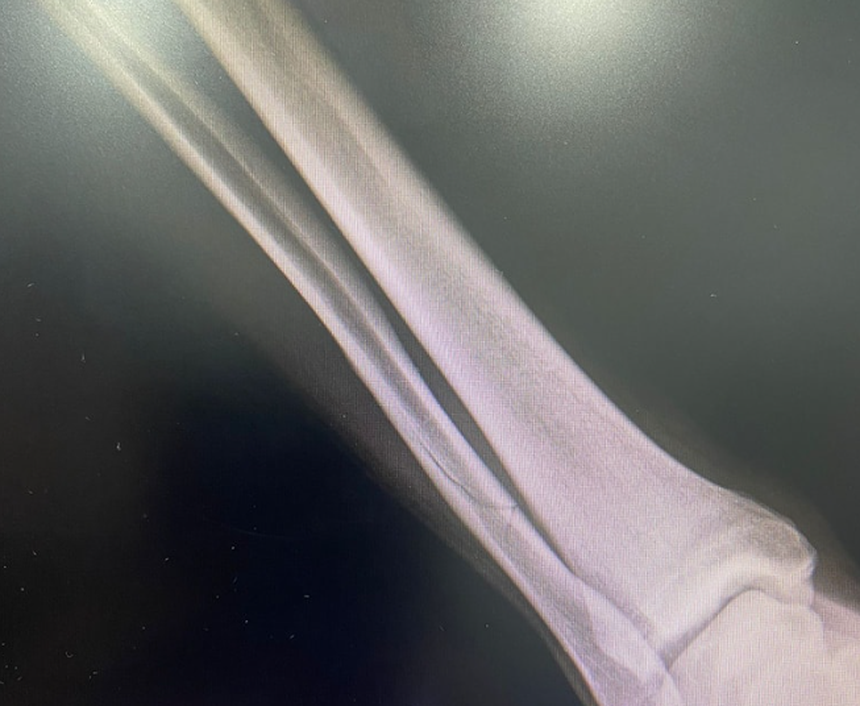

Jogador do Olivais e Moscavide parte perónio durante jogo

André Frias sofreu a lesão no duelo com a União de Tires

«No decorrer do nosso jogo contra a UD Tires o nosso jogador André Frias contraiu uma grave lesão, fratura de perónio que o irá afastar das competições no mínimo por 5 meses. Esta lesão surge após uma entrada cobarde e assassina que motivou a expulsão do faltoso.» Assim denunciou o Olivais e Moscavide a grave lesão que o seu jogador sofreu num jogo da 1.ª Divisão da AF Lisboa deste sábado, dia 10 de fevereiro.